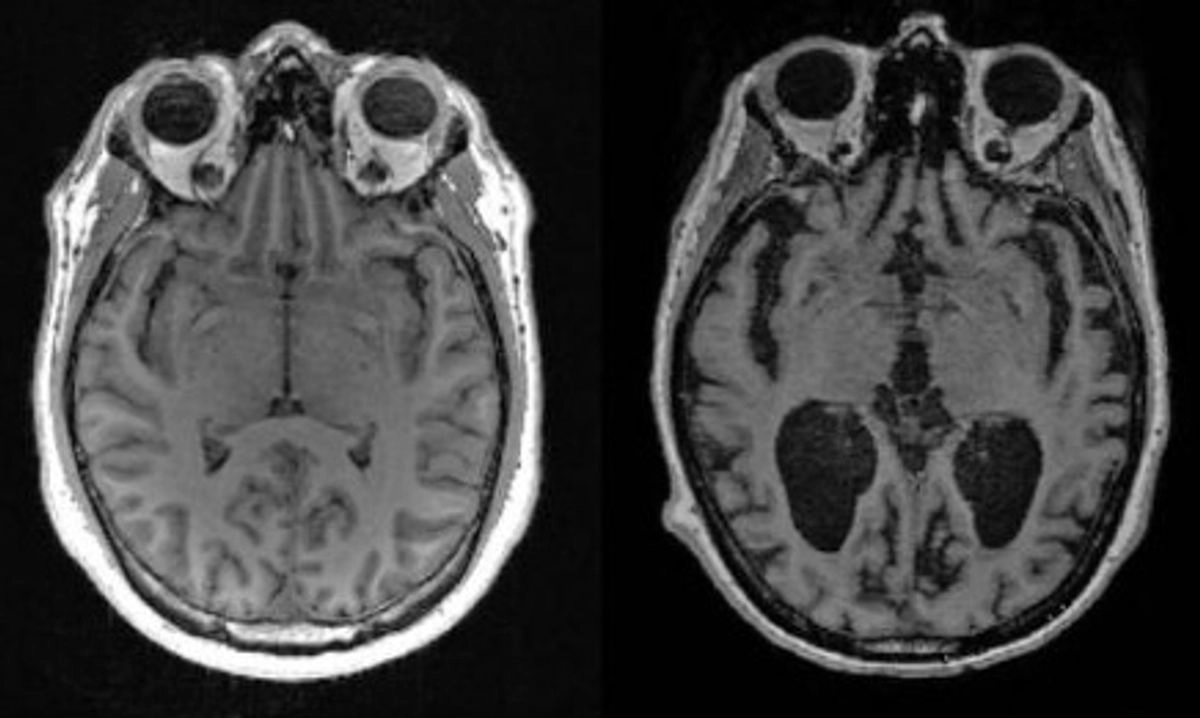

Una deficiencia del metal litio en el organismo podría ser un factor clave para el desarrollo de la demencia en los pacientes de Alzheimer, según revela un nuevo estudio pionero.

Científicos de la Facultad de Medicina de Harvard descubrieron que la pérdida de litio en el cerebro humano es uno de los primeros cambios que conducen al Alzheimer, mientras que en ratones, una depleción similar de litio aceleraba el deterioro de la memoria.

En algunos casos se detectó un nivel reducido de litio debido a la absorción deficiente del metal y a su unión a las placas amiloides, conocidas como señales inequívocas del Alzheimer.

El análisis reveló que el litio era el único metal con niveles marcadamente diferentes entre los grupos, que además parecían cambiar en las fases más tempranas de la pérdida de memoria.